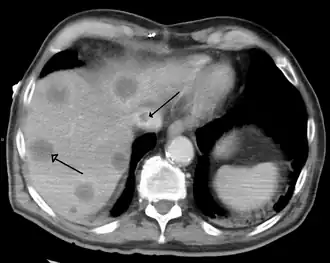

- Primary liver cancer most commonly manifests as hepatocellular carcinoma or cholangiocarcinoma; rarer forms include angiosarcoma and hemangiosarcoma of the liver. (Many liver malignancies are secondary lesions that have metastasized from primary cancers in the gastrointestinal tract and other organs, such as the kidneys, lungs.)[16]

- Budd–Chiari syndrome is the clinical picture caused by occlusion of the hepatic vein.[19]